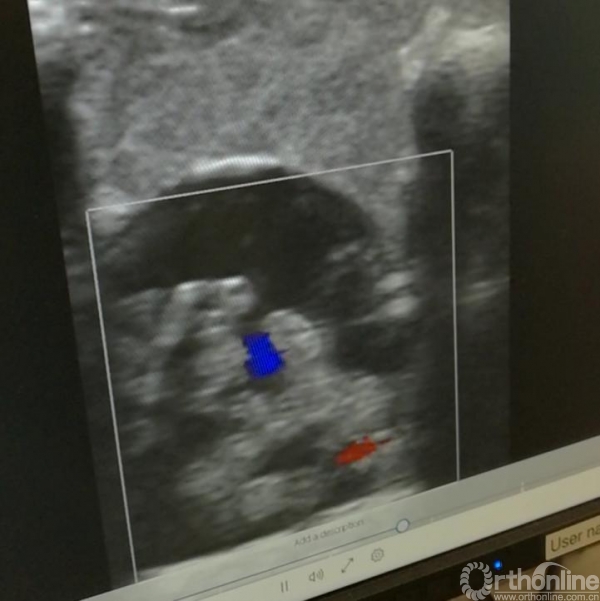

如果说导航系统是脊柱外科医生的“第二双眼”的话,那么还有“第三双眼”:术中超声,以及“第四双眼”:3D显微镜。

这里进行颈椎后路减压和脊髓肿瘤手术时都使用术中超声和多普勒,特别是进行脊髓肿瘤的手术时,打开椎板后用“L”形高频探头进行超声扫描,将肿瘤的形状、大小、血运、边界看得的一清二楚,剩下的工作只是“瓮中捉鳖”了。

颈椎后路减压后使用术中超声扫描,有时能发现一些减压不充分的地方,指导进一步减压,直到满意为主。在进行颈椎“钥匙孔”手术时,由于是微创,微型超声探头也无法进入,这里使用微型多普勒探头,根据放大器的声音(有点类似产科听胎心音,挺有意思的)就可以避开神经根附近的椎动脉,更好的保障了安全。

超声显示器:术中探查椎管肿瘤的位置和血运